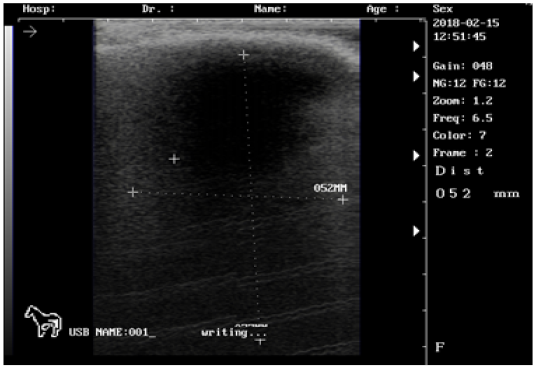

Ultrasound images of the testis of 5 months lamb showing: moderate echogenicity of the testicular parenchyma; mediastinum testicular diffusely echogenic